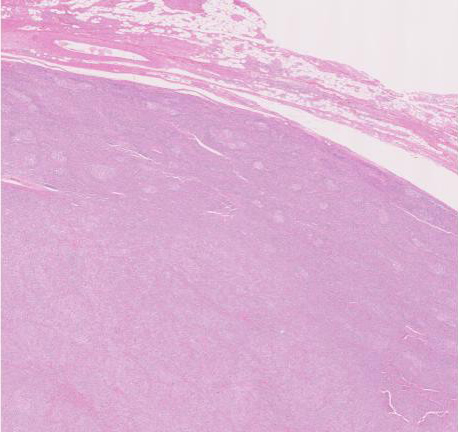

30歳代男性/ 大網腫瘍

上腹部圧迫感で受診. 画像所見で大網に13x11cmの腫瘤を認める。腫瘍摘出および膵脾合併切除術が行われる。腫瘍本体は網嚢内に位置. daughter lesionが複数認められた。膵脾には浸潤なし。リンパ節転移あり。6ヶ月後に腹膜播種で再発。

腫瘍は, 細血管を含む細い線維組織束で分画された胞巣状充実性病変で(Fig01),類円形ないし卵円形のvesicularな核をもつ円形, 多稜形の細胞が増殖している。核小体は小型, やや不明瞭。細胞質は境界が不鮮明で好酸性泡沫状を呈するものが多い。大型核やbizzarreな核の出現も認められる(Fig02-05)。血管周囲にリンパ球浸潤が認められる部分がある(Fig06,07)。